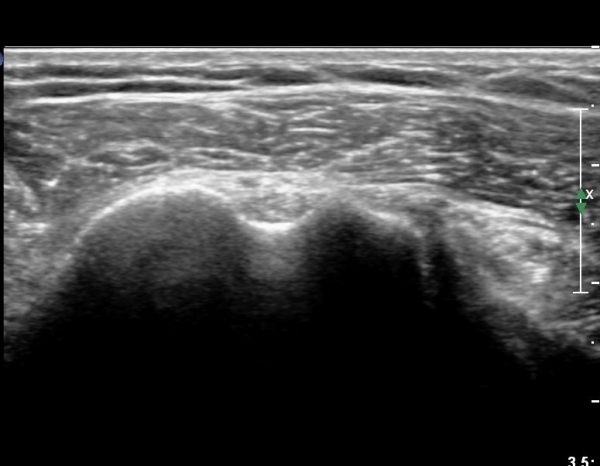

¿À±¸µ¹±â°ßºÀÀδë Á¾´Ü¸é°Ë»ç¿¡¼­ ƯÀÌ ¼Ò°ßÀ» º¸ÀÌÁö ¾ÊÀ¸³ª(»çÁø 1)